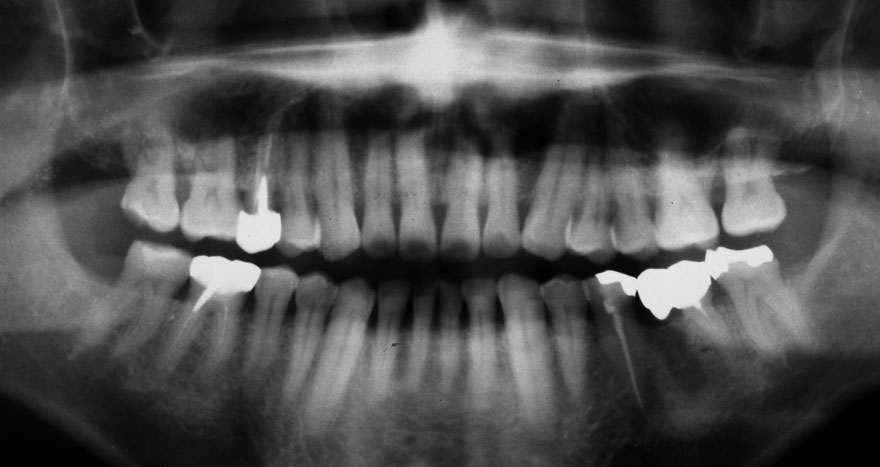

初診時 28歳 男性 平均歯槽骨喪失量:2.35mm

30年後 58歳

平均歯槽骨喪失量:3.88mm

22年間喪失量:-1.53mm

年間喪失速度:-0.05mm

(ケア頻度:2.80ヵ月ごと)